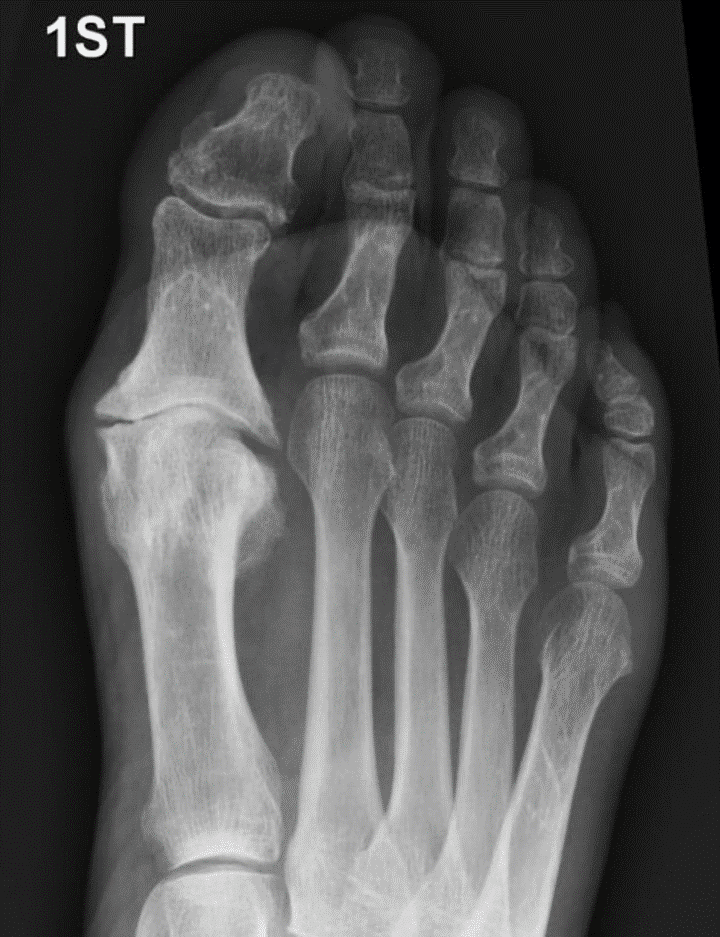

Hallux Rigidus

(Big Toe Arthritis)

Hallux rigidus (HR) refers to stiffness and pain in the joint at the base of the great toe (hallux). This joint is called the metatarsophalangeal joint (MTPJ). The usual cause of HR is arthritis and loss of the cartilage that lines the joint. HR may be caused by a previous injury, or it may be part of a general medical condition such as gout or rheumatoid arthritis. Often the cause is unknown.

HR presents with stiffness and pain in the great toe MTPJ. If the symptoms are severe, it may limit walking distance, and compromise work and recreational activities. Bony spurs (osteophytes) develop around the great toe MTPJ and can cause pain by rubbing against tight fitting shoes. In an attempt to off-load the painful great toe, some people will preferentially walk on the outer border of the foot, causing transfer pain to the lesser toes.

MTPJ debridement +/- osteotomy